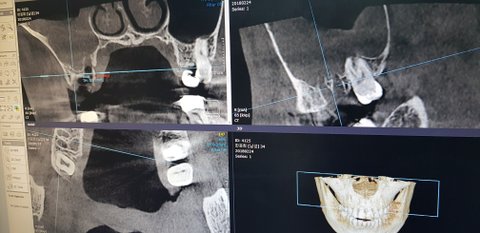

끝날때 제가 혹시 주말이 껴서 더 아플수있는거 아니냐하니 ct를 그때 두번 더 찍었어요

다음날 치아 발치후 ct사진이구요

치과 의사님에게 말하니 꼭 뽑아야 하는 치아를 뽑았고 염증도 긁어 냈다고 그러나 확실하게 긁어낸게 아니라서 혹시 이비인후과에 사서 농을 빼야할수있다 하더라구요

그리고 상악동에 농이 차있다는데 이게 농이 치아발치후 사라지나요